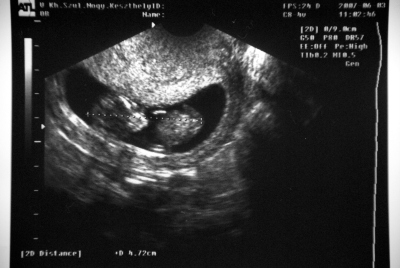

Megjöttünk tegnap este. Jó vol a hétvége, az UHon szerencsére minden rendben volt, nyaki redő normtális, CRL 4,7 cm és olyan aranyosan mocorgott. Nagyon szépen látszottak már a végtagjai is, kaptam fotókat is, majd rakok fel. Bár sztem a következő UHon még aranyosabb lesz.

Rákérdeztem arra az integrált tesztre, a korom miatt, és javasolta a dokibácsi is, úgyhogy megcsináltatom.